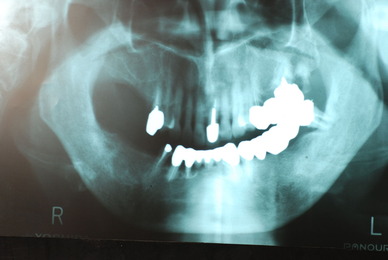

お口の中から差し歯、入れ歯、詰め物を追放しましょう!

口の中の病気を治し、病気を興さない医療を目指します。

「川崎市の入れ歯なら新丸子西口歯科医院へ」

「顎関節症は新丸子西口歯科医院へ」